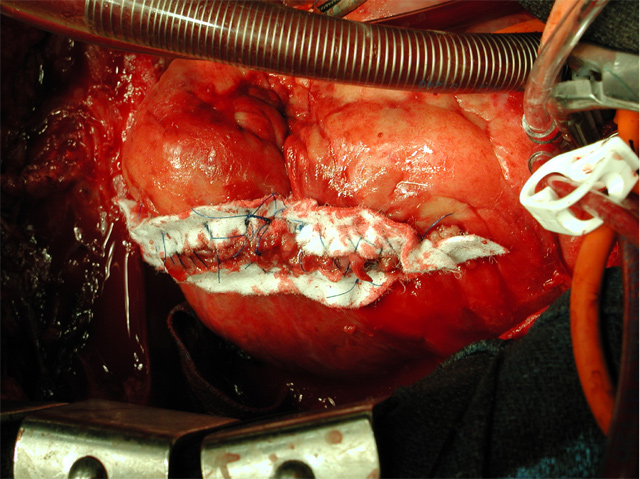

Excess patch is trimmed off and the ventriculotomy is closed using Teflon strips sewn onto the ventricular wall using interrupted full thickness horizontal mattress sutures of 3-0 polypropylene (Figure 9).

The sutures are then tied, closing the ventriculotomy (Figure 10). This first row of sutures reapproximates the muscle and secures the Teflon to it. As second double running layer baseball stitch is placed incorporating the Teflon strips and upper muscle layers to provide strain relief and seal gaps. This suture line rarely bleed because it is subject to low right sided pressures rather than high left sided pressures.